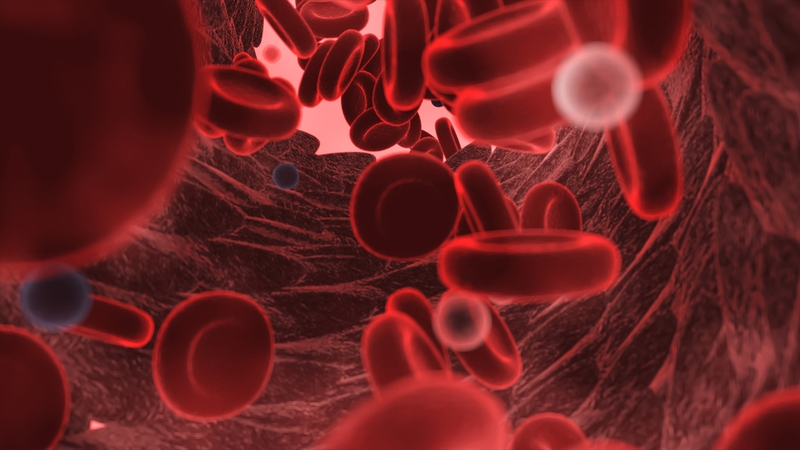

Để hiểu được vì sao máu có màu đỏ, trước tiên, bạn đọc cần nắm được các thành phần cấu tạo nên máu.

Theo đó, máu được hình thành từ các tế bào máu, bao gồm ba loại tế bào chính là hồng cầu, bạch cầu và tiểu cầu. Trong đó, hồng cầu là loại tế bào có chức năng chính trong việc vận chuyển oxy và chất dinh dưỡng đến các tế bào, cơ quan khác trong cơ thể để nuôi dưỡng. Trong tế bào hồng cầu có chứa một loại protein là hemoglobin, đây chính là nguyên nhân làm cho máu người có màu đỏ.

Hemoglobin là loại protein có khả năng kết hợp O2 với các chất khí khác như NO2 và CO2 trong quá trình vận chuyển. Mỗi một hạt hemoglobin có chứa một nguyên tử sắt để khi kết hợp với O2 sẽ tạo ra một hợp chất có màu đỏ được gọi là oxyhemoglobin – yếu tố chính tạo nên màu đỏ của máu.

Ngoài ra, trong máu còn chứa thêm một số thành phần khác như các tế bào tiểu cầu, tế bào màu trắng và các chất lỏng khác như muối, nước, chất dinh dưỡng. Tuy nhiên, những thành phần này không làm ảnh hưởng đến màu sắc của máu.